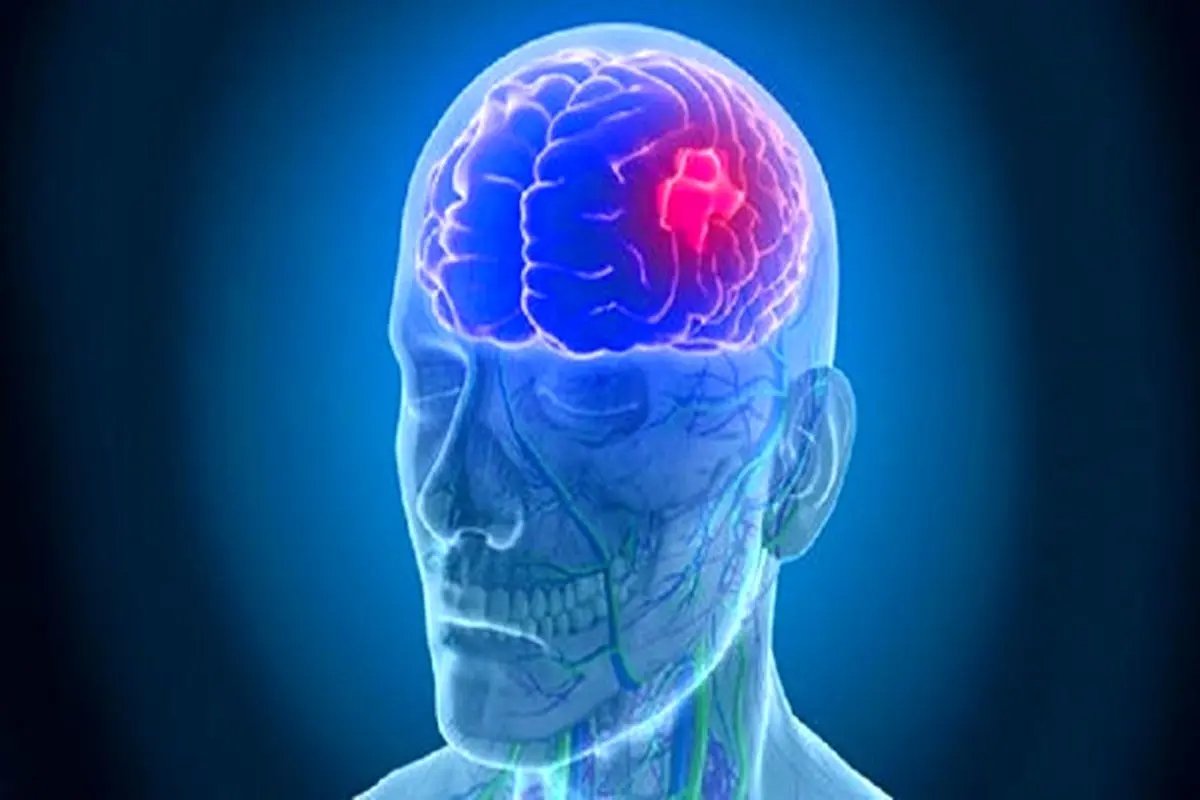

ورزشی که از سکته مغزی جلوگیری میکند

پارسینه: محققان در تازهترین مطالعه خود دریافتند، ورزش یوگا میتواند خطر بروز سکته مغزی را به میزان قابل توجهی کاهش دهد.

محققان در تازهترین مطالعه خود دریافتند، ورزش یوگا میتواند خطر بروز سکته مغزی را به میزان قابل توجهی کاهش دهد.

عوامل خطر سکته مغزی شامل شرایطی مانند فشار خون بالا، کلسترول و دیابت است که با تمرین یوگا قابل کنترل هستند؛ سکته مغزی معمولاً زمانی رخ میدهد که خون رسانی به قسمتی از مغز قطع یا کاهش یابد که ممکن است به بافتهای مغز آسیب برساند.

عوامل خطر سکته مغزی شامل شرایطی مانند فشار خون بالا، کلسترول و دیابت است که با تمرین یوگا قابل کنترل هستند؛ سکته مغزی معمولاً زمانی رخ میدهد که خون رسانی به قسمتی از مغز قطع یا کاهش یابد که ممکن است به بافتهای مغز آسیب برساند.